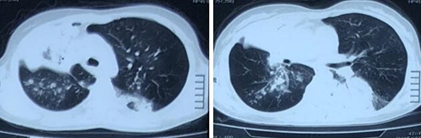

• 复查胸部CT示右肺上叶多发空洞,右肺中叶实变影,左肺下叶背段少许支气管扩张合并感染(图2)

图片

图2  患者胸部CT